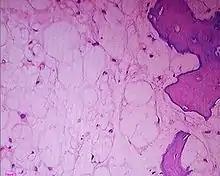

Histologic Subtypes

- Conventional

- Chondroid

- Better prognosis

- Subtype with predilection for skull base location

- Dedifferentiated

- Memorial Sloan Kettering; 2008 PMID 18641983 -- "Chordoma and chondrosarcoma gene profile: implications for immunotherapy." (Schwab JH, Cancer Immunol Immunother. 2008 Jul 19. [Epub ahead of print])

- Affymetrix gene expression profiles, 6 chordoma and 14 chondrosarcoma. Validation by qPCR and IHC

- Outcome: Both show overexpression of extracellular matrix genes compared to other sarcoma types. Chordoma selective expression of T Brachyury and CD24; chondrosarcoma Type IX and XI collagen. HMW-MAA expressed in chordoma 62%, chondrosarcoma 48%

- Conclusion: Similar gene profile of upgregulated ECE matrix genes